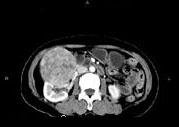

问题 女,57岁,右腰部胀痛6个月余,触及右侧腹部包块2个月,CT平扫及增强如图所示,下列说法正确的是 ( )

选项 A、考虑肿块来源于右肾,是巨大的肾癌,并挤压推移右肝,与其分界欠清 B、考虑肿块来源于右肾,是肾血管平滑肌脂肪瘤,并挤压推移右肝,与其分界欠清 C、增强扫描肿块强化明显,其内可见无强化的低密度坏死灶 D、考虑肿块来源于肝脏,是原发性肝癌,并挤压推移右肾 E、平扫时可见右侧腹部巨大的软组织肿块影,其内可见小片状的低密度影

答案 ACE